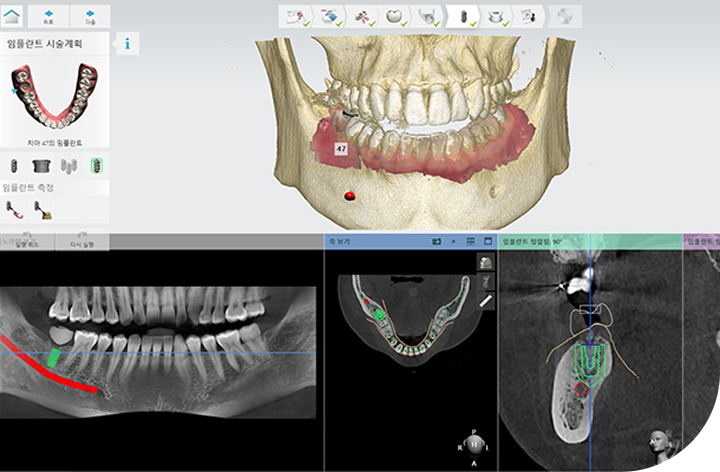

환자의 구강 정보를 디지털 데이터를 기반으로 3D 가상 모의 수술을

진행해 기존 방식 대비 수술 시간이 짧아 체력적 부담을 줄여주고

최소 절개로 통증 및 붓기 최소화로 면역력이 약하거나 회복력이 더딘

고령의 환자, 고혈압 당뇨 등 전신질환을 앓고 계신 분들도 부담없이 안전하게 수술받을 수 있습니다.

성공적인 임플란트 식립을 위해서는 정밀한 진단이 필수적입니다.

3D-CT, 구강 스캐너 등 다양한 디지털 장비를 이용하여

치아, 잇몸뼈, 신경 위치 등을 정확하게 파악해 수술 오차를 최소화하고,

통증 및 출혈을 줄여 더욱 안전하고 편안한 임플란트 식립이 가능합니다.